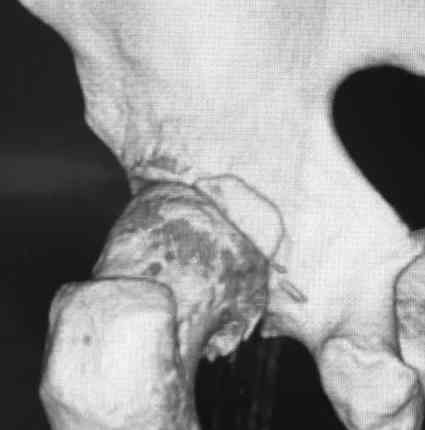

Pipkin II

Стоило ли заниматься остеосинтезом в этом случае?

Мужчина, 50 лет, активный, падение с высоты. При поступлении вправление вывиха, других повреждений нет Без значимой сопутствующей патологии, не курит. Стоило ли выполнять остеосинтез при таком оскольчатом переломе или сразу пойти на ТНА?

На снимке №2 есть перелом заднего края суставной впадины,его, я так понял, решили не фиксировать? Фрагмент не очень большой.